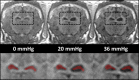

Methods: Baseline MRE measurements were obtained, and then catheters were surgically placed into the left and right lateral ventricles of three animals. ICP was systematically increased over the range of 0 to 55 millimeters mercury (mmHg), and stiffness measurements were made using brain MRE at vibration frequencies of 60 hertz (Hz), 90 Hz, 120 Hz, and 150 Hz.